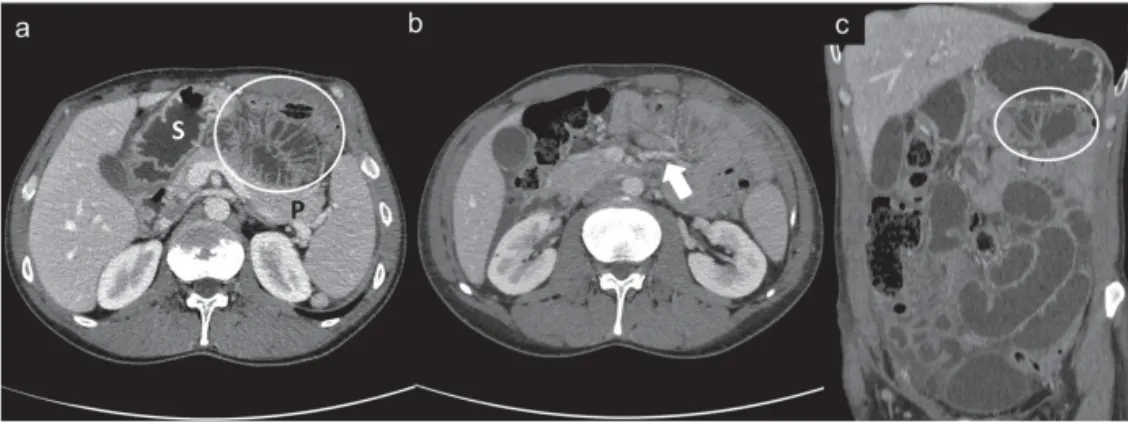

a: Bowel loop에 의한 mass effect로 stomach를 앞으로 밀어냄. encapsulated된 소장 보임

위와 췌장 사이에 위치할 수도 있다.

b: IMV와 Lt ascending colic a. 가 밀집되어 있고 확장되어 있다.

확장된 소장이 우측 복부에 위치 (상행결장과 십이지장의 3rd portion 보다 lateral에 위치)

c의 흰색 화살표: 확장되고 loop 로 수염되는 mesenteric vessel